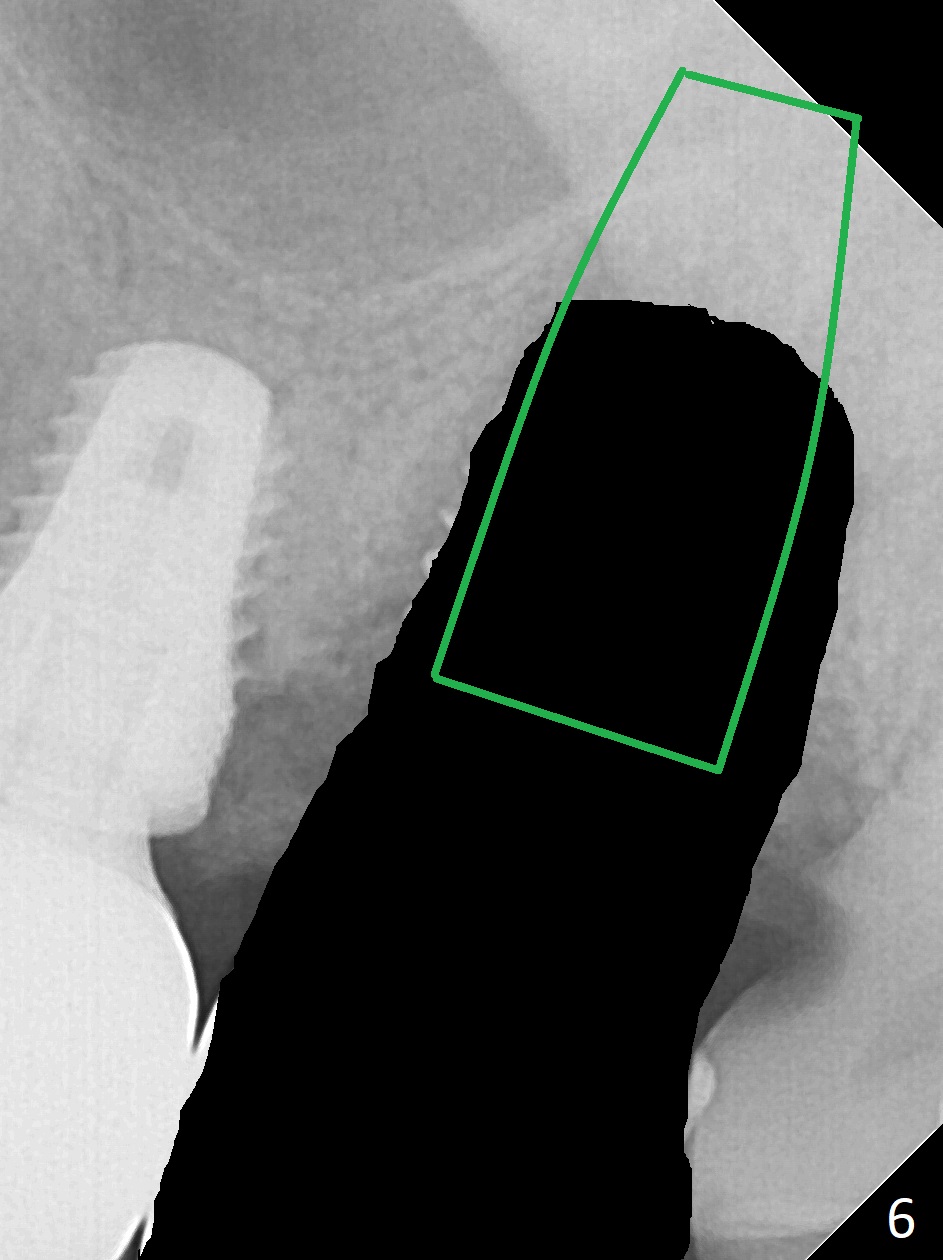

The 7x14 mm implant at #15 of a 89-year-old man is found to be loose ~ 1 year post cementation (Fig.1). After implant removal and debridement, bone graft is placed (Fig.2 G); the mesiocervical caries of the 3rd molar is removed, but not filled (*). With collagen membrane fixed with Chromic gut suture (Fig.3), setting acrylic is applied in the edentulous area, including the mesiocervical cavitation of the 3rd molar (Fig.4) for further retention. Bone graft gets lost following socket preservation at #31 with periodontal dressing. When the bone graft matures, a new implant (Fig.6 green) will get primary stability from the native bone, i.e., coronal to the sinus floor (Fig.5 F). The acrylic dressing (Fig.7 A) with a portion locking to the undercut of the neighboring crown (*) remains in place 5 weeks postop. When the dressing is cut off, the bone graft is exposed with odor (Fig.8,9 *). Periodontal dressing is applied. The distolingual portion of it gets lost due to brushing a day later. When he returns, the dressing is removed (Fig.10). It appears that the growing in gingival margin is pushing the bone graft out. A moment later after just a few rounds of swallowing, more graft is lost (Fig.11). We would love to leave the wound open, but the senior citizen complains of air leaking and requests reapplication of periodontal dressing. The bone graft is almost gone when the 2nd periodontal dressing is removed nearly 2 months postop (Fig.12). The tooth sensitivity disappears when MO caries is taken care of. The socket has a dimple 5 months postop (Fig.13), although it is filled with bone graft (Fig.14). Due to low bone density (~500 HU), sinus lift is required for implant stability with PRF (Fig.15). In fact the lab chooses not to do sinus lift.